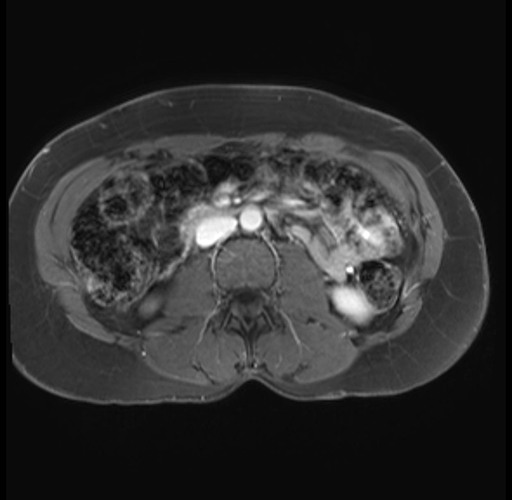

Imaging Analysis

Look through the patient's CT scan to identify any areas of concern for the necessary procedure.

Based on your CT findings, which issue(s) are present and would give reason for "planned slowing down moment(s)" in this case?

Considering a standard distal pancreatectomy procedure, what step(s) of the operation would you do differently in this case?